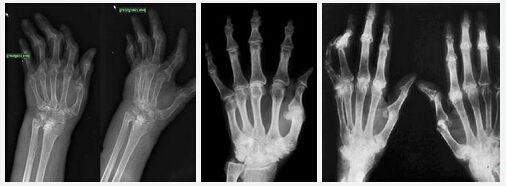

(圖:風濕性關節(jié)炎的治療及預防方法不對極易致病情不斷惡化)